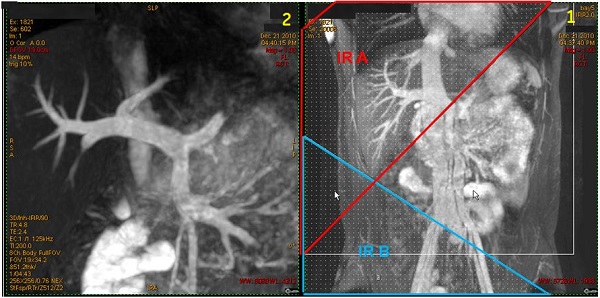

Figure 6. Coronal localizer with two IR bands and resultant coronal liver portal vein

Table 4. Image legend

NumberDescription

1Coronal localizer with two IR bands applied to saturate arterial flow.

2Resultant Inhance Inflow IR magnified coronal image of portal vein.